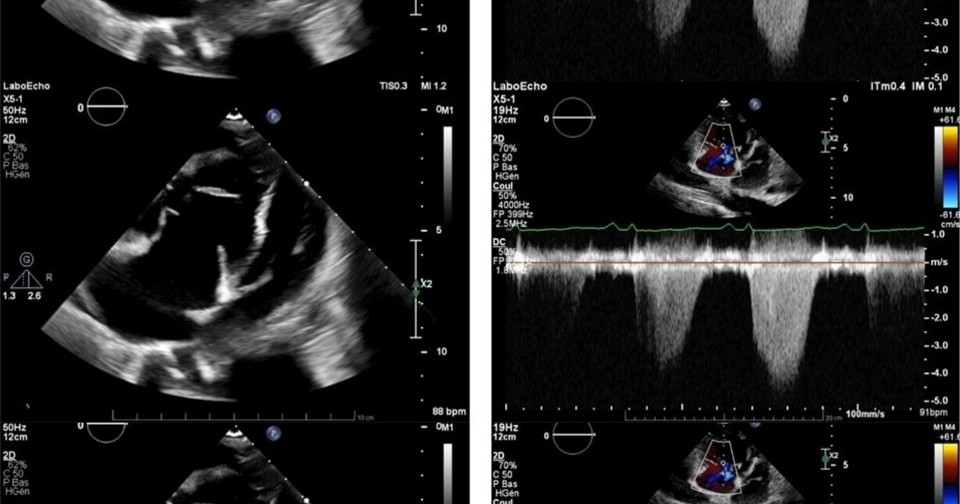

На электрокардиографии врачи обнаружили признаки гипертрофии правого желудочка, что может говорить о его перегрузке. Анализ крови показал анемию, а биохимическое исследование выявило признаки сердечной недостаточности. Инструментальные методы позволили исключить тромбоэмболию легочной артерии, а эхокардиография показала, что левый желудочек сдавлен расширенным правым желудочком. Измерение давления в правых отделах сердца и легочной артерии подтвердило легочную гипертензию.